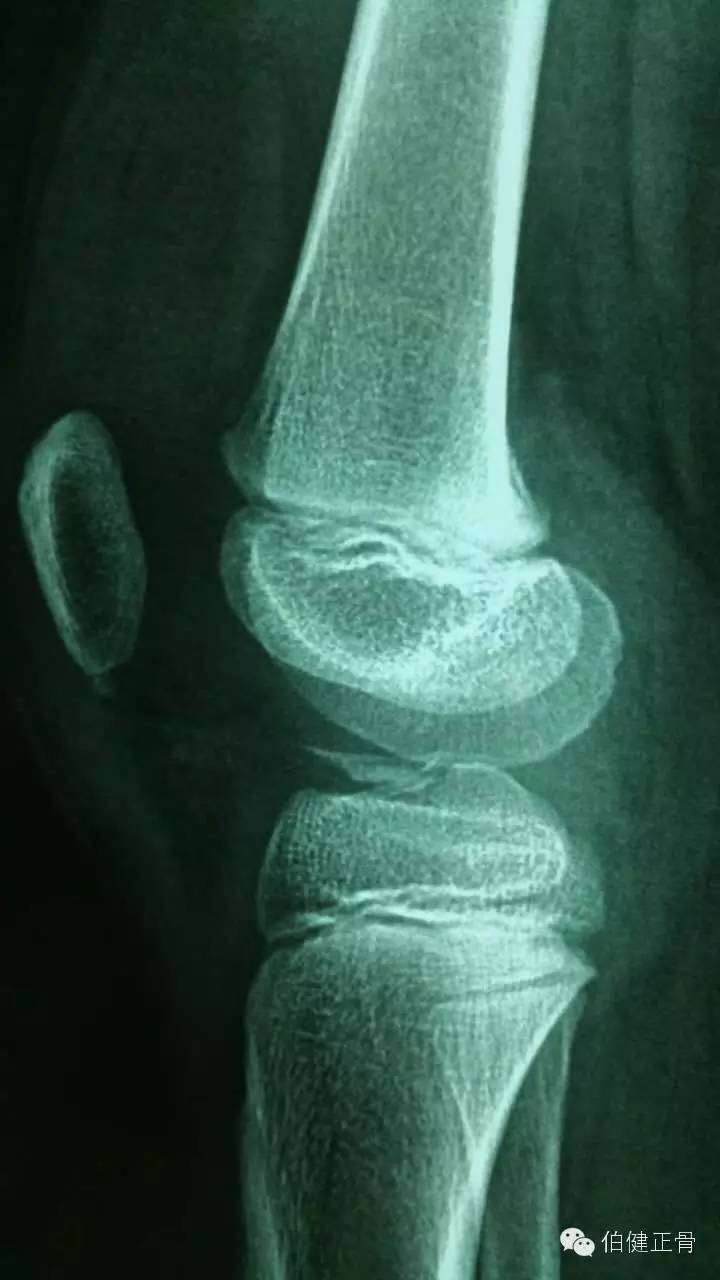

近日,我科收治一名10岁小儿,爬树时不慎从树上跌下致右膝外伤,局部肿痛,活动受限,经X线片及MR诊断为前交叉韧带止点撕脱骨折。当地医院不敢接诊,遂转至我院求治。

本病治疗非常棘手,因为该患者属于Tanner 1期的未成年患者(Tanner分期见下表),骨骺远未发育成熟。